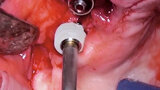

Kombinace standardních a ultrakrátkých implantátů při rehabilitaci celých úst